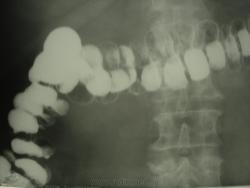

мужчина 1959 г.р. заранее прошу прощения за качество снимков, невовремя сломался аппарат и скопически посмотеть не получилось,но попытались сделать несколько снимков дабы не пропадала подготовка пациента(правый отдел толстой кишки). Пациента беспокоят периодические боли в павой половине живота, и помоему вздутие в течение года. получилась вот такая изменчивая картина на спине и на животе

По этим снимкам целостного впечатления не складывается... Особенно смутил купол слепой кишки - дефект наполнения?

а как Вам контур восходящей ободочной на первом снимке(сделан лежа на спине)? и у меня тоже пока ничего не складывается если честно... рентгенолог с соседнего города со стажем сказал, что многие его коллеги делают так ирриго вслепую... но как...лично мне без скопии трудно что либо сказать